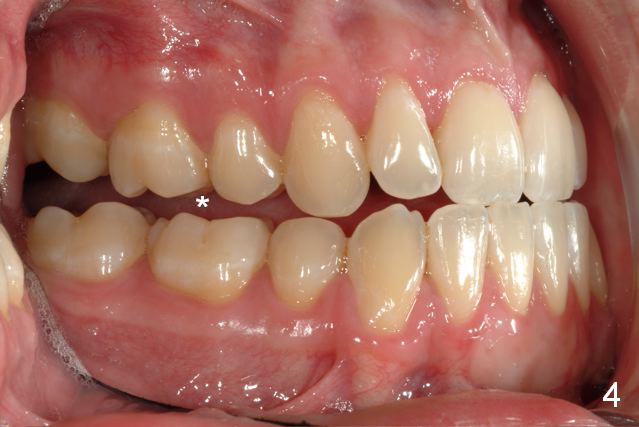

Initial information was obtained on 02/26/2014 (Fig.1-10). Anterior edge-to-edge and Posterior Open Bite (Fig.4 *): unfavorable differential Class III growth after orthodontics as a child.